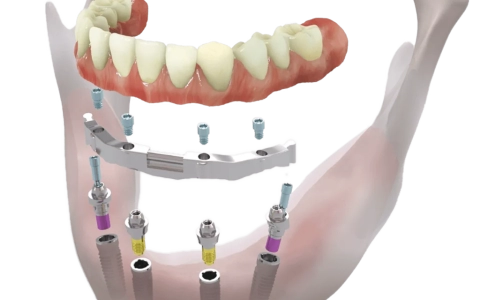

All-on-four İmplant Tedavisi

All-on-4/6, tam dişsiz çenede 4–6 implantla aynı gün sabit, estetik ve fonksiyonel diş sağlayan, kemik grefti ihtiyacını azaltan tedavidir.